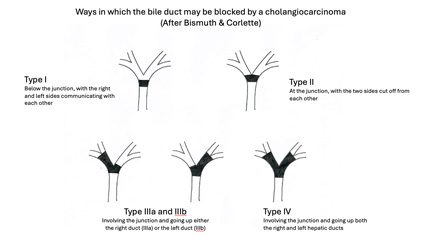

The type and extent of surgery depends on the location of the cancer within the liver or the biliary tract. The Bismuth classification (shown in the diagram above) is a practical and commonly used surgical classification of bile duct tumours at the junction of the right and left ducts. It is based on which ducts are involved and the extent to which they are involved. Cancers of the common bile duct (Bismuth Type I and II) require removal of the common bile duct and the regional lymph glands, with creation of a join between the right and left bile ducts on the one hand and the bowel on the other (so that bile can continue to flow into the bowel). The term used for this join is a Hepatico-jejunostomy. Tumours involving the confluence (Bismuth Type III) require, in addition, removal of a part of the liver. Type IV tumours – in the rare event of one being resectable - need an extended liver resection to achieve clear margins. Cholangiocarcinomas in the lower part of the bile duct, where it passes through the pancreas, should be managed with a pancreatoduodenectomy (also known as a Whipple operation).